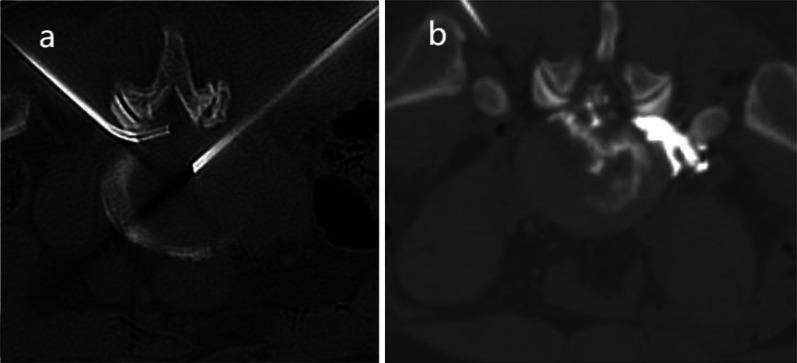

Methods: This single-blind randomized controlled trial was conducted at the Department of Pain Management, The First People's Hospital of Changzhou, between October 2023 and October 2024. This single-center, single-blind randomized controlled trial finally enrolled 60 eligible patients with lumbar disc herniation; participants were randomly assigned to the experimental (HILT + collagenase) or control (collagenase alone) group using a computer-generated randomization sequence with 1:1 allocation. Group assignments were concealed in sealed opaque envelopes until intervention initiation. All participants underwent collagenase chemonucleolysis, with the control group receiving standard postoperative care combined with sham laser therapy, while the experimental group received additional high-intensity laser irradiation alongside conventional treatment. The primary endpoints comprised visual analog scale (VAS) pain scores and clinical efficacy rates evaluated using modified MacNab criteria, while secondary outcomes included the Oswestry Disability Index (ODI), straight-leg-raising angle measurements, and 36-Item Short Form Health Survey (SF-36) quality of life assessments, with standardized evaluations conducted at five predefined intervals: preoperative baseline, 1 week, 1 month, 3 months, and 6 months postoperatively. Statistical analyses were performed using SPSS 20.0. Continuous variables were compared via independent t-tests or Mann-Whitney U tests, while categorical variables were analyzed using chi-squared tests. All tests were two-tailed, with P < 0.05 considered statistically significant.